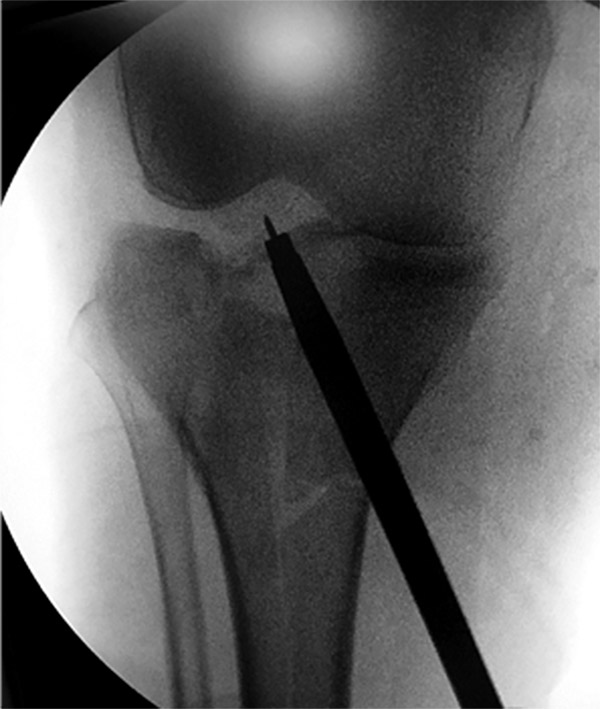

Posteriormente se realizó la reducción de la fractura con control artroscópico y radioscópico. Si existe hundimiento utilizamos la guía de LCA, que permite pasar un alambre de kirschner desde la cara anterointerna de la tibia al centro exacto de la depresión, y sobre él, con una mecha de 10 mm, se realiza un agujero en la cortical únicamente, ya que al colocar el impactor tendremos la posibilidad de llevar mayor cantidad de injerto a la zona hundida y a la base de la lesión. A través del túnel se eleva el fragmento con impactor canulado con 10° de inclinación en la punta, lo que nos permite llegar al fragmento deprimido casi en forma paralela, todo bajo visión intrarticular y radioscópica. Al realizar el túnel en diagonal creamos una mejor distribución de cargas sobre el platillo deprimido y así si perdemos reducción, la misma sería mínima, debido a que tenemos una base de tejido firme por debajo del túnel (fig. 9).

Figura 9: Clavija guía con impactor.

Es importante observar a través de la artroscopía que a medida que vamos impactando vemos al fragmento elevarse. Cuando el impactor se halla aproximadamente a 2 cm de la superficie del platillo, significa que entre el impactor y la superficie articular hay hueso de esponjosa compactado y no sería necesario el uso de injerto para sostener la elevación. El fragmento se debe sobre elevar 2 mm y observar que la superficie tome contacto con el nivel del menisco (fig. 10). Al retirar el impactor se crea una presión negativa en el túnel malogrando la reducción lograda. Por eso empleamos una osteodesis temporaria con uno o dos alambres de kirschner, permite mantener la misma y actuar como guía para los tornillos (fig. 11).